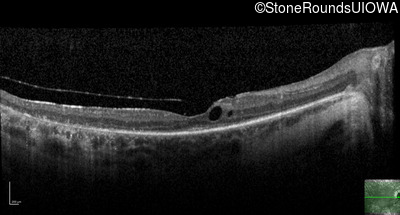

Optical Coherence Tomography - Right - 20/40

Exemplar / OCT Stack